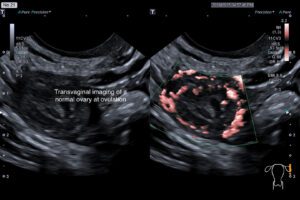

A transvaginal ultrasound scan is the technique for quick, effective assessment and diagnosis of various conditions. It is the initial method favoured by clinicians as it is completely safe, posing minimal risks to the patient.

Transvaginal ultrasound is a screening test for endometrial cancer. It is not a screening test for cervical cancer nor is it a screening test for ovarian cancer. However it can reassure you that your ovaries are normal. It is also part of the investigation of infertility and monitoring of infertility treatment strategies.

A follicle tracking scan measures the size of active ovarian follicles. Follicles are fluid-filled structures in the ovaries that may contain an egg, and their size can be used to estimate when ovulation will occur. A scan is performed to assess the timing of ovulation, providing information that can be used in both natural conception cycles and fertility treatments.

The ovaries are however not evaluated in isolation. The lining of the womb ie the endometrium is also assessed.  An endometrial thickness scan measures the womb lining (endometrium) to track changes during a normal cycle, correlate ovulation with ovarian appearances, or monitor responses to fertility drugs used in treatment.

Follicle tracking  and endometrial measurement scans are typically done three times per menstrual cycle. The first, a detailed gynaecological scan, occurs between days 3 and 5 of your period (with day one being the start of bleeding). Further scans, focusing on monitoring the natural changes of the ovaries and endometrium, (or treatment induced changes)  follow at 1–2 day intervals as needed.